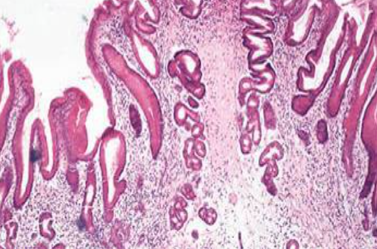

3.肥厚性胃炎(hypertrophic gastritis) 又称Menetrier病。以胃粘膜皱襞显著肥厚如脑回状为特征,好发于胃底和胃体,局灶性或弥漫性。常伴原因未明的低蛋白血症。镜下见胃小凹高度增生、下延甚可达粘膜肌层。